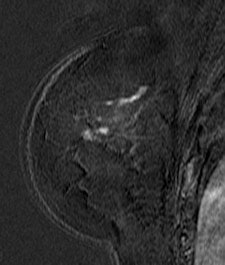

![]() ![]() |

| Patient with breast cancer (invasive ductal carcinoma, grade II). MR-subtracted images (three minutes after contrast medium injection) before (left) and at the end (right) of the neoadjuvant chemotherapy. Initial staging: unifocal infiltrating cancer. After treatment, even if there is a decrease in size of the cancer, its long axis (RECIST) is unchanged with a multifocal shrinkage of the tumor. Unsuccessful first breast-conserving surgery, then mastectomy. Image courtesy of Dr. Anne Tardivon. |